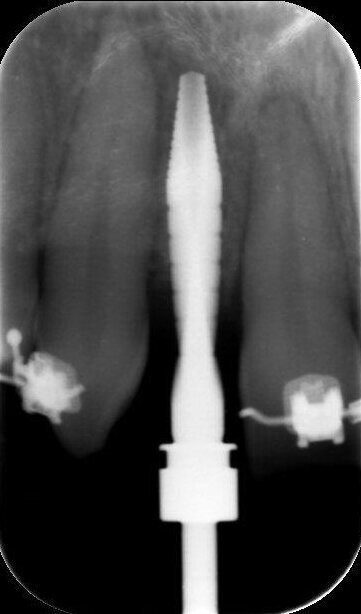

In deze casus is indertijd voor tissue level-implantaten gekozen en na ongeveer achttien jaar in functie is de esthetiek, mede door de vorm van de cuspidaten en het zichtbaar worden van de implantaten, discutabel te noemen (afbeelding 1 en 2).

In samenspraak met de patiënte en in goed overleg met de behandelend orthodontist werd besloten de implantaten op de posities 13 en 23 te verwijderen, de cuspidaten naar distaal te verplaatsen en de angulatie van de elementen te corrigeren, zodat het plaatsen van twee implantaten op de posities van de laterale incisieven goed mogelijk zou worden (afbeelding 5 en 6).